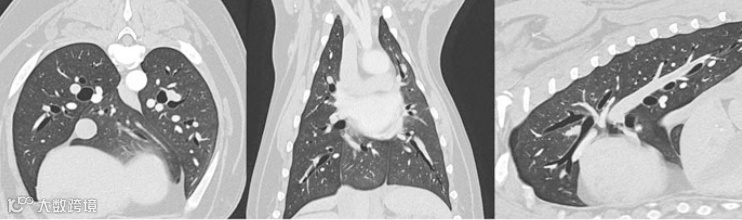

多平面重建MPR:

可以看出,小动物除了在做检查的时候比人类困难😅,诊断难度好像没有高很多?